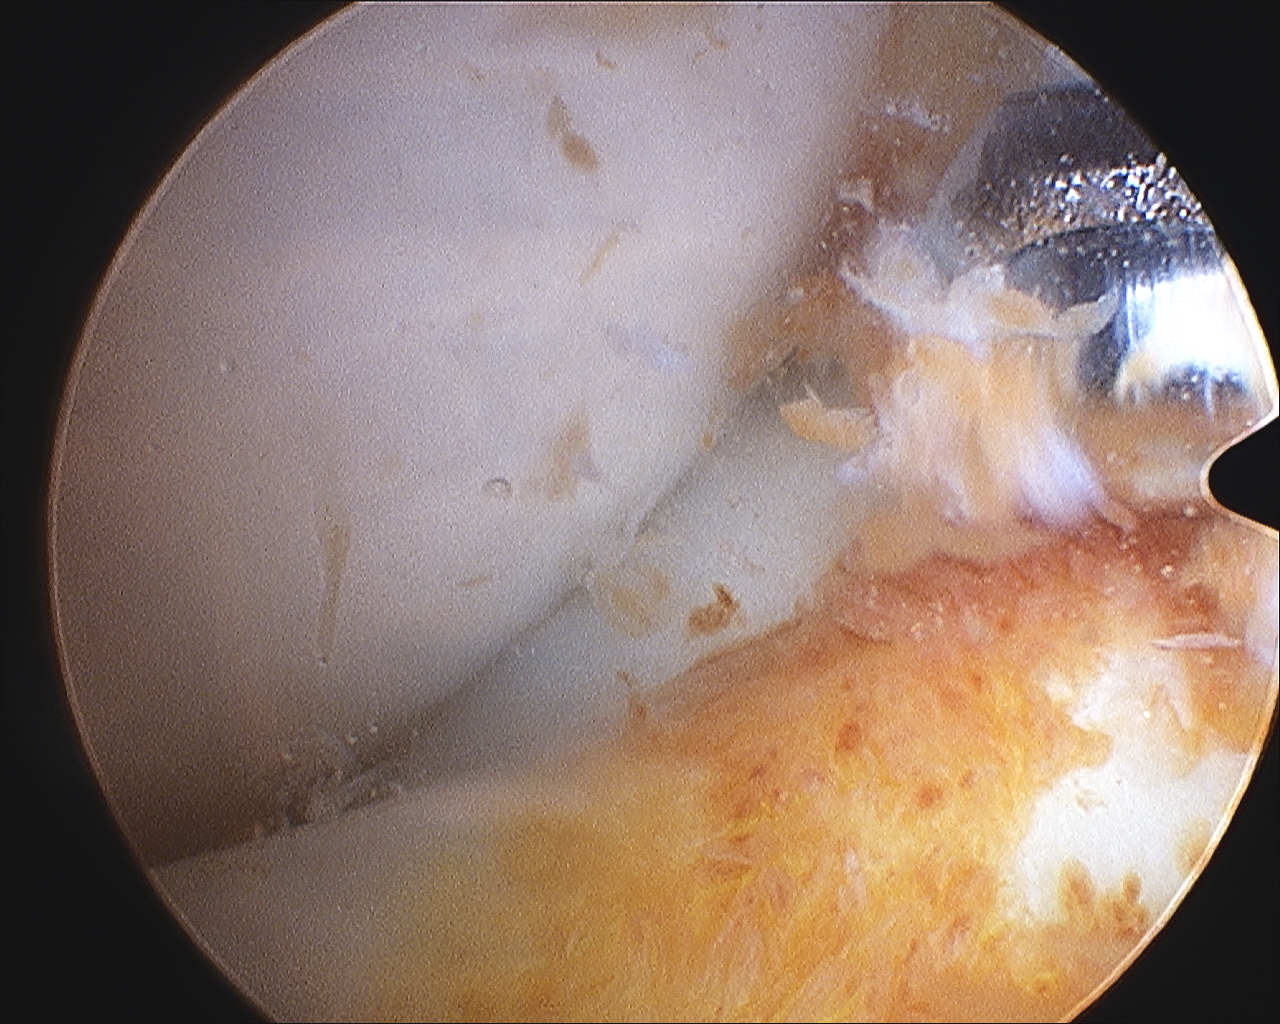

Diffuse knee joint

Synovectomy

Complete synovectomy

- dissecting the synovium and intermediate layers

- preserve deep fibrous layers and ligaments

- need to remove all affected synovium for best results

- meticulous surgical technique required